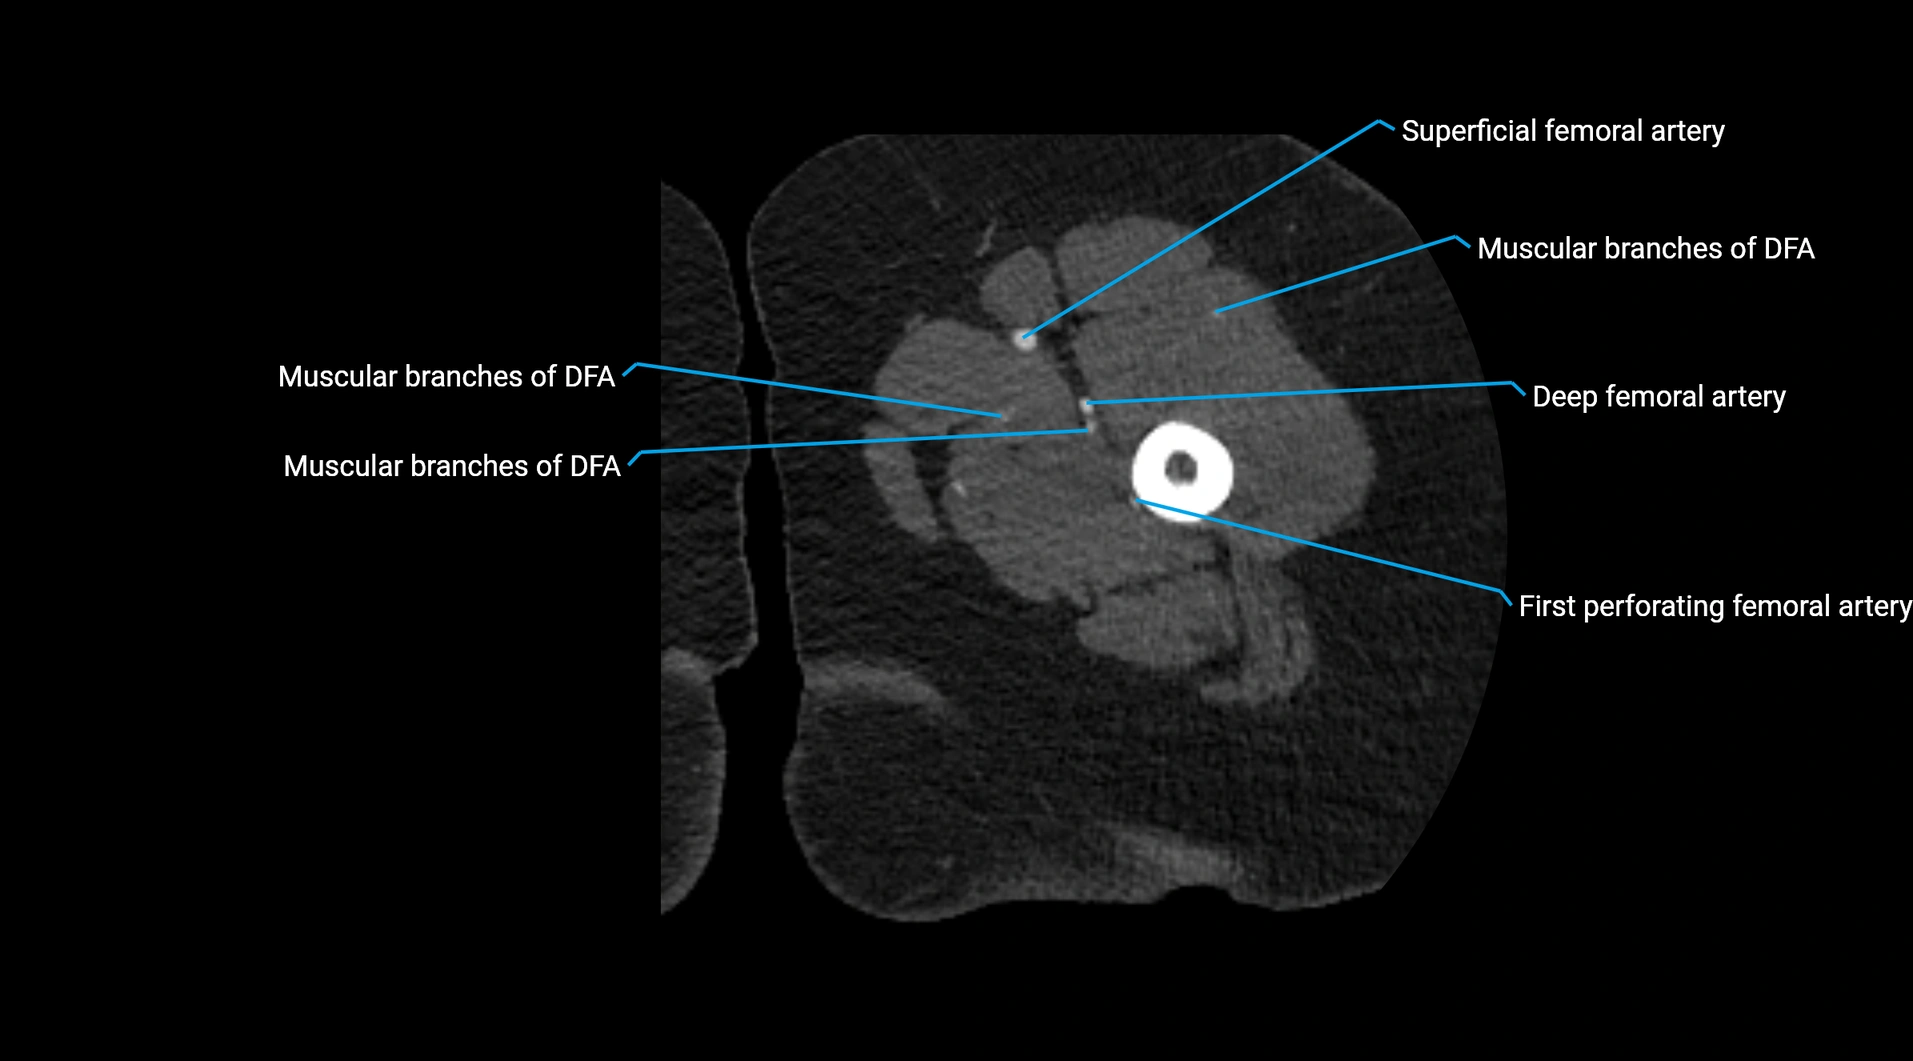

CT images

image